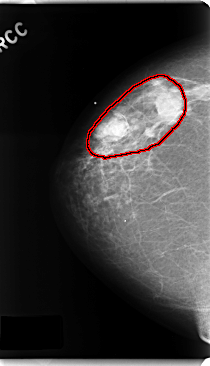

ics_version 1.0 filename C-0182-1 DATE_OF_STUDY 13 5 1996 PATIENT_AGE 62 FILM FILM_TYPE REGULAR DENSITY 1 DATE_DIGITIZED 19 3 1998 DIGITIZER LUMISYS LASER SEQUENCE LEFT_CC LINES 4792 PIXELS_PER_LINE 2648 BITS_PER_PIXEL 12 RESOLUTION 50 NON_OVERLAY LEFT_MLO LINES 4752 PIXELS_PER_LINE 2512 BITS_PER_PIXEL 12 RESOLUTION 50 NON_OVERLAY RIGHT_CC LINES 4752 PIXELS_PER_LINE 2728 BITS_PER_PIXEL 12 RESOLUTION 50 OVERLAY RIGHT_MLO LINES 4728 PIXELS_PER_LINE 2696 BITS_PER_PIXEL 12 RESOLUTION 50 OVERLAY |

FILE: C_0182_1.RIGHT_CC.OVERLAY TOTAL_ABNORMALITIES 1 ABNORMALITY 1 LESION_TYPE MASS SHAPE LOBULATED MARGINS CIRCUMSCRIBED ASSESSMENT 5 SUBTLETY 5 PATHOLOGY MALIGNANT TOTAL_OUTLINES 1 BOUNDARY |